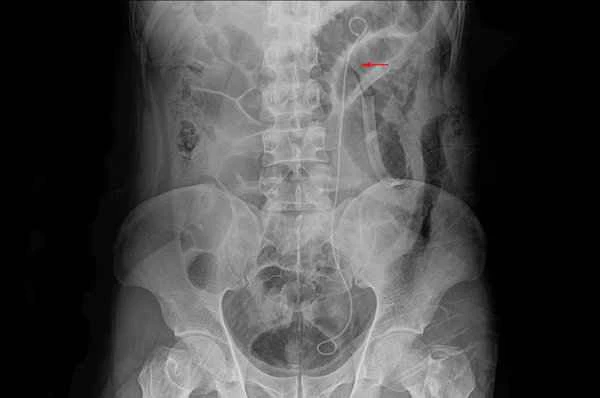

What type of obstruction is colonic obstruction?

Colonic obstruction is a type of gastrointestinal obstruction. Its importance lies in the fact that colonic obstruction...

What are the symptoms of bowel obstruction?

Bowel obstruction is a serious digestive system disorder that can prevent intestinal contents from passing through prop...

Does intestinal obstruction cause urinary retention?

Intestinal obstruction does not usually directly cause urinary retention, but there may be an indirect link between the...